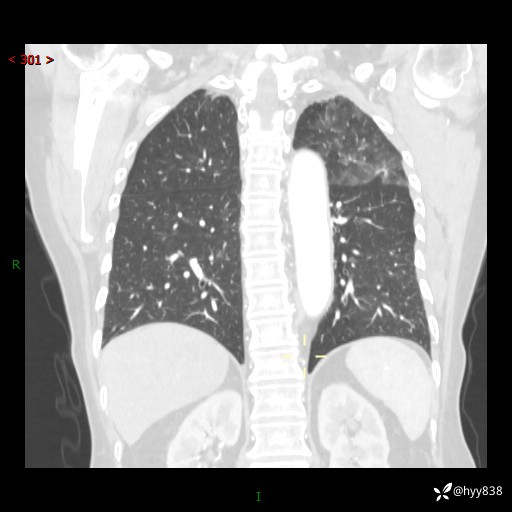

老年女性,偶然发现肺结节10天。结节不大,空洞不小,还牵拉胸膜---结果公布~

现病史:患者10余天前因“左侧鼻塞伴鼻腔异味2月”就诊于我院耳鼻喉科,查胸部CT示:左上肺结节影,建议复查。患者偶有咳嗽、咳痰,多咳白痰,无畏寒、发热,无胸痛、呼吸困难等,现为进一步明确肺结节性质,就诊于我科门诊。现以“孤立性肺结节”收住我科。 起病来,患者精神、食欲、睡眠尚可,体力、体重无明显变化。

胸部CT(2024.7.16)